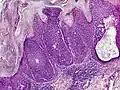

Microscopic histopathological examinations of the tumor tissues of all poroma variants stained with hematoxylin and eosin dyes reveal: a) basophilic "poroid cells" (i.e. small, cuboid-shaped cells with oval nuclei which resemble cells in the peripheral layer of the distal portion of eccrine sweat gland ducts[20]) that may form cords and broad columns extending downward from the epidermis; b) larger cuticular cells (i.e. squamous epithelial-like eosinophilic cells that resemble the luminal cells lining eccrine sweat gland ducts[20]); and in some cases c) clear cells (i.e. cells with small nuclei surrounded by pale cytoplasm).[3] Poroma tumor tissues may appear highly vascularized and/or have areas of necrosis, i.e. dead or dying cells. Hidroacanthoma simplex variants are mainly composed of poroid cells, few cuticular cells, and no clear cells and are confined to the epidermis; dermal ductal variants are mostly confined to the superficial dermis and are composed of small solid and cystic nodular aggregates of poroid, cuticular, and clear cells; poroid hidradenoma variants have large aggregates of solid and cystic components and extend deeper into the dermis or even subcutis; and eccrine poroma variants are composed of all three cell types but are primarily located in the epidermis and superficial dermis. Poromas may have 2 or more of these variants in the same tumor tissue and the variants typically have histopathology findings that are not clearly distinguishable from each other.[3]

Hidroacanthoma simplex